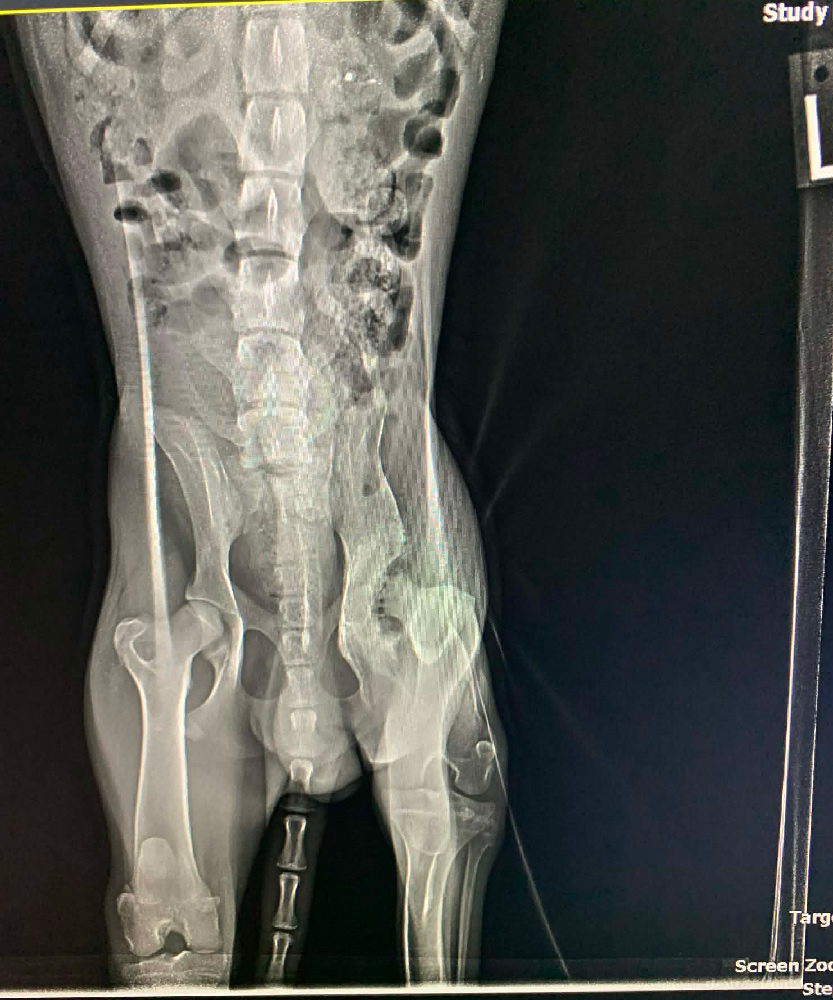

It’s particularly notable as a result of his neck damage wasn’t the one trauma he carried. As soon as Phil arrived at Animal League America to proceed his care, a extra full image started to emerge. Additional exams revealed a number of accidents, together with injury to his left hip joint, doubtless brought on by vital trauma, corresponding to being hit by a automotive.

The top of his hip joint is deteriorated and not suits correctly, which causes ache with motion. To repair this, our veterinary staff will carry out a specialised process to take away the broken portion of the joint. Over time, his physique will kind a brand new, purposeful joint supported by muscle, permitting him to maneuver comfortably.

Phil additionally has proof of an older fracture in his proper leg that healed by itself, a quiet reminder of what he endured earlier than assist arrived. “When our companions in Texas initially despatched us pictures of Phil, we had been fairly horrified with the extent of his accidents,” Dr. Laheney stated. “A case like this might simply, in a municipal shelter, be positioned on the euthanasia listing.”